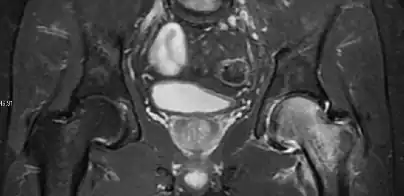

Magnetic resonance imaging

Many pathological conditions of the hip are detected early by MRI due to its high soft tissue resolution and sensitivity. Its accuracy in studying acute hip pain in children has proved to be superior to ultrasound and plan film radiography. However, MRI accessibility and the need of sedation relegate its use to selected cases in which diagnosis is not clear with less demanding techniques. These include differentiating transient synovitis from a septic arthritis or osteomyelitis, diagnosis of inflammatory joint disease or bone tumors, and early detection and follow-up of Perthes disease.[1]

In adults, MRI is currently playing a definite role in the assessment of osteoarthritis. Although traditionally belonging to the arena of radiographs, the role of MRI has been stressed after the term femoral acetabular impingement was coined in 2003. Growing interest has been focused in accurate diagnosis of the acetabular and femoral morphological abnormalities that may lead to early osteoarthritis.[1]

MR imaging is considered paramount to these objectives, mainly when surgery is considered, due to the ability of MRI to portray the whole section of the femoral neck surface, as well as to image the labrum and articular cartilage.[1]

Most of the angles and measurements described in the plain radiograph section can be accurately reproduced on MRI. In addition, the superiority of MRI resolution with intra-articular contrast allows detection of labral and chondral abnormalities that may influence the choice of medical, percutaneous, or surgical management (Figure 9).[1]

Intra-articular osseous causes of pain include several conditions: avascular necrosis (AVN), transient osteoporosis of the hip (TOH), tumors, and stress or insufficiency fractures. All these entities may present with a pattern of bone marrow edema characterized by decreased signal intensity on T1 weighted images and increased signal intensity on fluid sensitive sequences, such as fat saturated T2-weighted or STIR images. When there is no evidence of a focal lesion associated with the edema pattern, TOH is suspected. When a band of low intensity is seen inside the edematous area, the shape and length of this band become important. It is generally convex to the articular surface in the case of subchondral stress or insufficiency fractures, whereas it is concave, circumscribing all of the necrotic segment, in cases of AVN. When doubts do persist, gadolinium-enhanced MRI tends to show that the proximal portion beyond the band is enhanced in fractures but is not in AVN.[1]